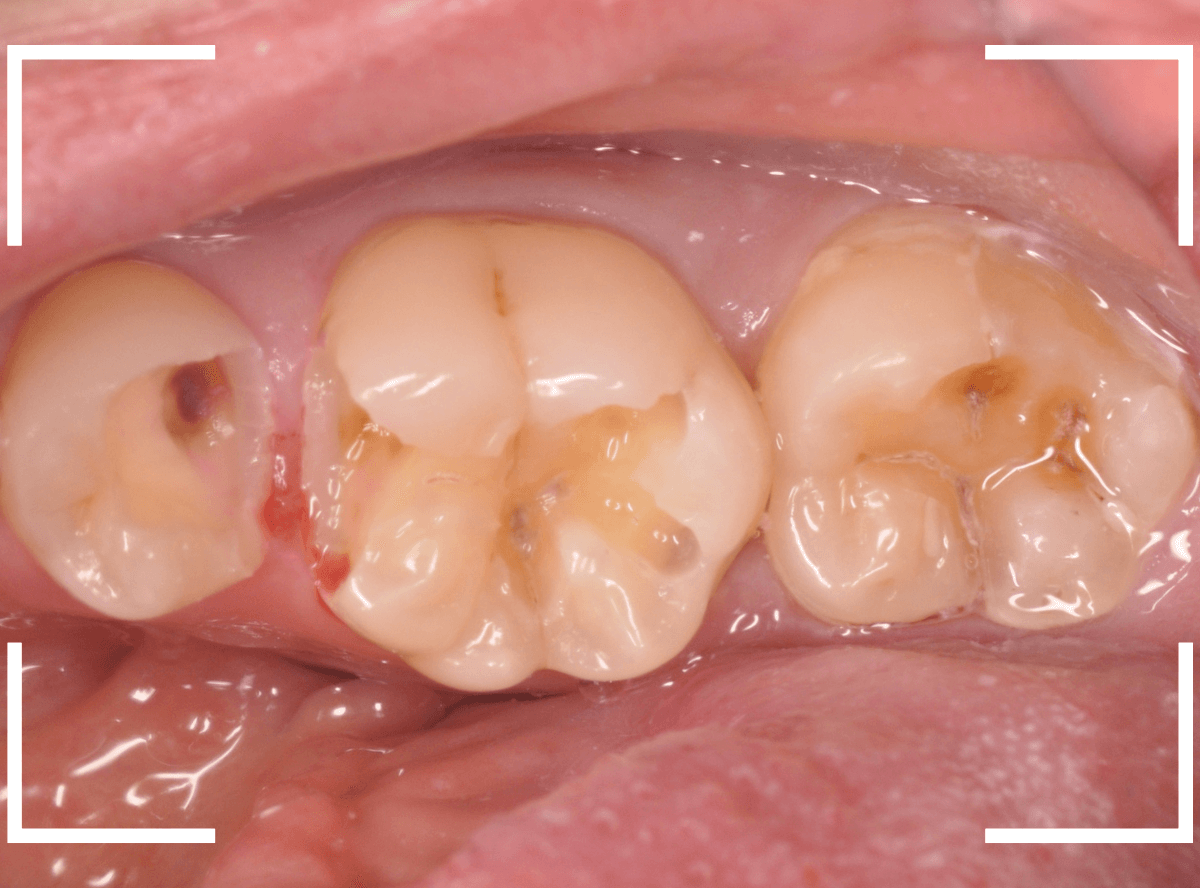

直近の患者さんの例で説明しましょう。

3本の大きな虫歯を除去した後に、ベースセメントで歯を保護します。

ここでこのまま、つめものが入るように歯をトリミングして型どりをしてもいいのですが、症状が出ないかしばらく経過観察します。

症状がないのを確認できたら、改めて歯のトリミングをして型どりをして、つめものをsetします。

この方法は、来院回数がかかりますが、症状がない事を確認してからつめものを作るステップに入るために、その後のトラブルは非常に少ないと感じています。